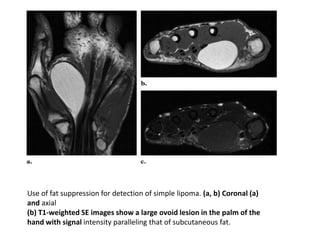

Use of fat suppression for detection of simple lipoma. (a, b) Coronal (a)

and axial

(b) T1-weighted SE images show a large ovoid lesion in the palm of the

hand with signal intensity paralleling that of subcutaneous fat.

(c) Axial T2-weighted fast SE image obtained

with fat saturation shows uniform suppression of signal

throughout the lesion, an indication that the lesion is composed

entirely of fat.